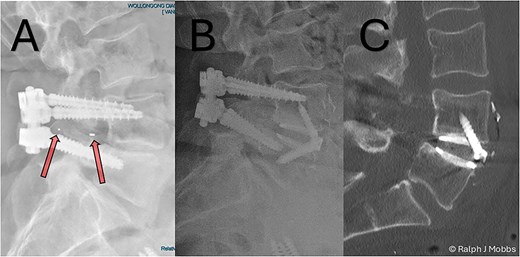

This case report illustrates a novel two-stage revision strategy for symptomatic L4/5 pseudarthrosis (Fig. 1A), integrating anterior lumbar interbody fusion (ALIF) with posterior endoscopic cage retrieval and decompression. The initial ALIF procedure (Fig. 1B) enabled restoration of segmental lordosis, disc height, and immediate biomechanical stability, while also facilitating distraction of scarred posterior elements. This was followed by a targeted, minimally invasive endoscopic procedure to remove the failed TLIF cage and decompress neural elements (Video 1), thereby avoiding the morbidity of an open posterior revision.

(A) Initial presentation with TLIF cage migration posteriorly into the spinal canal and paraspinal muscles. (B) Stage 1 and 2 completion, including revision fusion using an ALIF cage (Redmond Ti/PEEK, A-spine, Taiwan) and TLIF cage removal. (C) CT scan post TLIF removal and disc height restoration with ALIF cage.

A 64-year-old female with a history of a TLIF at L4/5, performed 18 months prior to presentation to the current surgeon, presented with persistent low back pain and radiculopathy. Imaging demonstrated non-union at the TLIF site with ongoing foraminal stenosis and segmental instability (Fig. 1A). Multidisciplinary review determined that a revision fusion was the initial focus as mechanical back pain related to non-union was the primary complaint. Following the planned stage 1 intervention, removal of the migrated TLIF cage was determined necessary as the device was serving no purpose and likely causing further symptoms. Therefore, a two-stage revision strategy was planned.